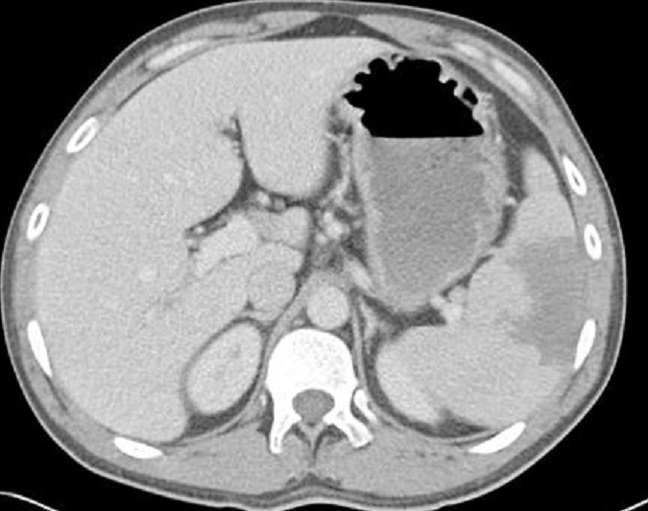

Image radiologique TDM d'un

traumatisme de la rate a grade IV avec aspect

radiologique de hematome itraparenchymeteuse marque

, dechirude capsulaire et de devascularisation de

bord anterieur . Coupe axiale TDM avec contrast

intraveineuse phase veineuse . |

Image rasdiologique d'une traumatisme de

la rate avec lesions hematome intraparenchymeteux

diffuse et dechirure de bord anterieure avec

devascularisation de artere splenique ( grade V ) .

Coupe TDM axiale phase veineuse |